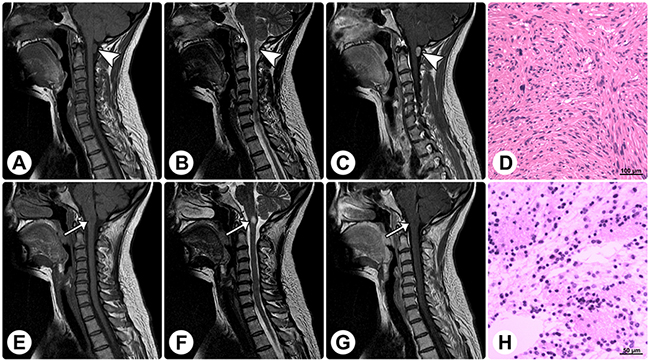

Figure 4: Radiological and histopathological profiles of a patient with concomitant rosette-forming glioneuronal tumor and schwannoma. MRI reveals a spinal extramedullary solid mass at the C1 level (arrowheads) and an intramedullary solid mass in the medulla oblongata (arrows). (A–C) The former mass shows isointensity on sagittal T1WI (A), slight hyperintensity on sagittal T2WI (B), and homogeneously remarkable enhancement on sagittal contrast T1WI (C). (E–G) The latter mass shows isointensity on sagittal T1WI (E), remarkable hyperintensity on sagittal T2WI (F), and no enhancement on sagittal contrast T1WI (G). (D and H) Histopathological examinations of these 2 lesions are consistent with schwannoma (D) and RGNT (H), respectively. (Original magnification: D: 100×; H: 200×).

Histopathological examination of the specimens disclosed characteristic biphasic neurocytic and glial architectures, leading to the diagnosis of RGNTs (Figure 5). Microscopically, the neurocytic component was composed of uniform small round cells with scant cytoplasm and spherical dense nuclei, and these neurocytes were arrayed surrounding eosinophilic neuropil cores or small vessels forming neurocytic rosettes or perivascular pseudorosettes. The glial element consisted of spindle- or stellate-shaped astrocytic cells with elongated to oval nuclei forming a compact fibrillar meshwork with occasional Rosenthal fibers, and in focal areas, oligodendroglial-like cells with round nuclei and clearly staining cytoplasm were present (Figure 5D), with morphology resembling pilocytic astrocytoma. Cellular atypia, mitotic figures, necrosis, and calcification were rarely visible. Additionally, small foci of glomerulus-like microvascular proliferation were observed in three cases (Figure 5F and 5G).

Figure 5: Histopathology and immunohistochemistry of rosette-forming glioneuronal tumors. Microphotographs show characteristic histopathological features of RGNT consisting of biphasic glial and neurocytic architecture (A). The neurocytic component is characterized by a ring of tumor cells with scant cytoplasm and dense nuclei, forming rosettes around eosinophilic neuropil cores (B). The glial component consists of spindle- or stellate-shaped astrocytic cells forming a compact fibrillar meshwork with occasional Rosenthal fibers, resembling pilocytic astrocytoma (C). In focal areas of the glial component, oligodendroglial-like cells with round nuclei and perinuclear clear halos are observed (D). Vacuoles are present around the perivascular pseudorosettes (E). Focal microvascular proliferation is observed (F&G). Synaptophysin staining exhibits strong immunoreactivity within the neuropil-like cores of neurocytic rosettes (H). Staining for GFAP demonstrates strong immunoreactivity in the glial background (I) and in the oligodendroglial-like component (J). Staining for Olig-2 displays positivity in both the neurocytic rosettes (K) and the pilocytic-like glial background (L). NeuN shows focal immunoreactivity in both the neurocytic- and pilocytic-like components (M&N). Ki-67 labeling in both components is low (O&P). Dual-color FISH shows normal disomic status (two red target signals and two green reference signals) of the chromosomes 1p36 (Q) and 19q13 (R). In rare cases, the DNET-like component is present, and it consists of the “specific glioneuronal element” with oligodendroglial-like cells arranged in columns separated by microcystic spaces, floating neurons, and mucoid stroma (S). In one case, concomitant spinal schwannoma is found (T). (Stains: A–G = Hematoxylin-eosin stain; H = Synaptophysin immunohistochemistry; I and J = GFAP immunohistochemistry; K and L = Olig-2 immunohistochemistry; M and N = NeuN immunohistochemistry; O and P = Ki-67 immunohistochemistry; Q and R = Dual-color FISH; S and T = Hematoxylin-eosin stain. Original magnification: A, C, E–G, S, and T: 100×; B, D, and H-P: 200×)

Immunohistochemical staining showed strong immunoreactivity for synaptophysin (SYN) within the neuropil cores of the neurocytic rosettes and pericapillary neutrophils of the perivascular pseudorosettes (Figure 5H). The glial background, including the astrocytic component and the focal oligodendroglial-like cells, was strongly positive for glial fibrillary acidic protein (GFAP) (Figure 5I and 5J). Both the neurocytic- and pilocytic-like components stained positively for oligodendrocyte transcription factor 2 (Olig-2), S-100 protein, and microtubule-associated protein 2 (MAP-2) (Figure 5K and 5L). Focal immunoreactivity for neuron-specific nuclear protein (NeuN), neuron-specific enolase (NSE), and neurofilament (NF) protein in the neurocytic cells was observed in 13, 35, and 23 cases, respectively (Figure 5M and 5N). Epithelial membrane antigen (EMA) staining was negative in all cases. The proliferation indices according to Ki-67 expression were generally very low ranging from 0% to 5% (Figure 5O and 5P), while focally exceeding 5% (reaching up to a maximum of 8%) within rare high-power fields in three cases. Moreover, no isocitrate dehydrogenase (IDH1/IDH2) gene mutation was detected, and dual-color fluorescence in situ hybridization (FISH) revealed no codeletion of chromosomes 1p36 and 19q13 (Figure 5Q and 5R).

Additionally, we noted in-situ DNET-like pathological characteristics in 5 patients, neurofibromatosis type I in one patient, and concomitant solitary spinal schwannoma without neurofibromatosis context in one patient. The DNET-like components consisted of the “specific glioneuronal element” with oligodendroglial-like cells arranged in columns separated by microcystic spaces, floating neurons, and mucoid stroma (Figure 5S). The concomitant spinal schwannoma was found at the C1 level and was resected, while the RGNT in this patient was found in the medulla oblongata (Figure 5T and Figure 4).